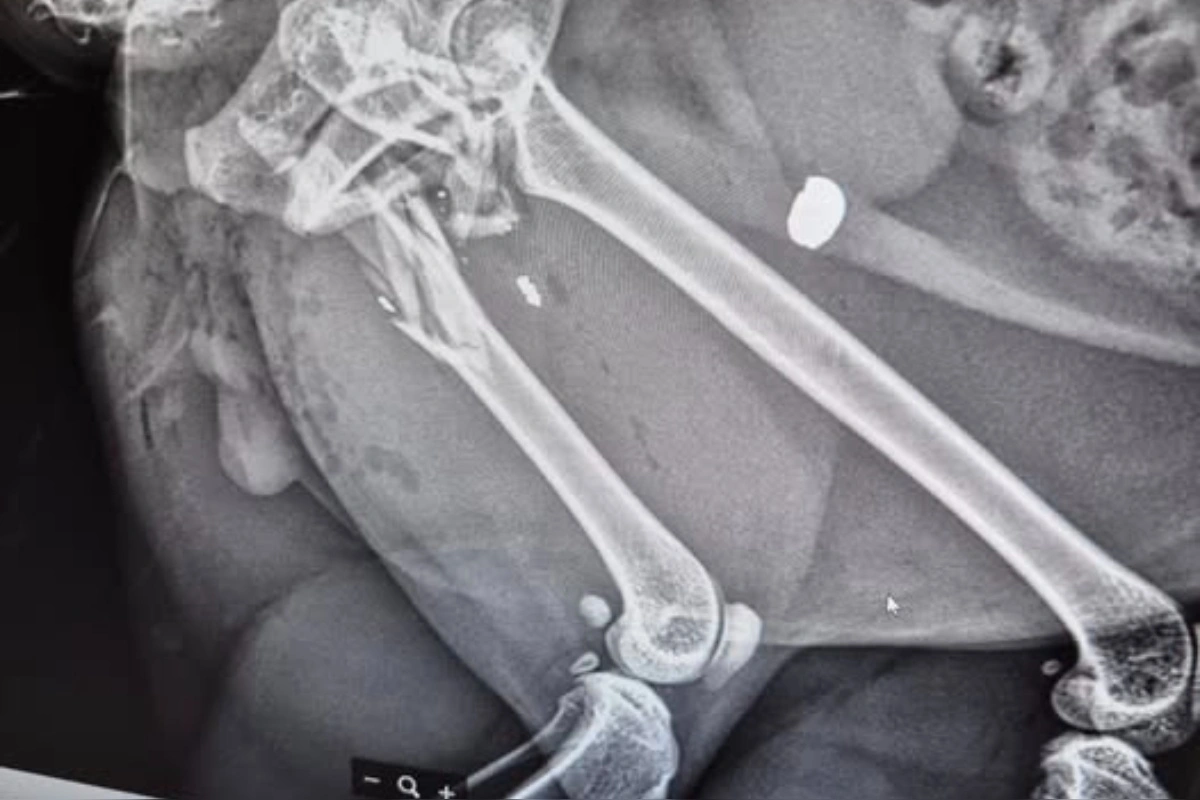

Na Družstevnej ulici v Ivanke pri Dunaji došlo podľa miestnej obyvateľky Andrei k znepokojujúcemu incidentu. Tá šokovala ľudí tým, že v pondelok krátko po 17. hodine niekto postrelil jej kocúra. Zvieratko utrpelo trieštivú zlomeninu stehennej kosti.

„Chcem upozorniť občanov na Družstevnej ulici od čísla 38 po 44 a od 35 po 43, že včera nám tamojší občan postrelil na ulici nášho kocúra,“ uviedla žena. „Kocúr má trieštivú zlomeninu stehennej kosti. Pred týždňom sa nám stratil ďalší kocúr. Myslíme si, že za tým je tá istá osoba.“